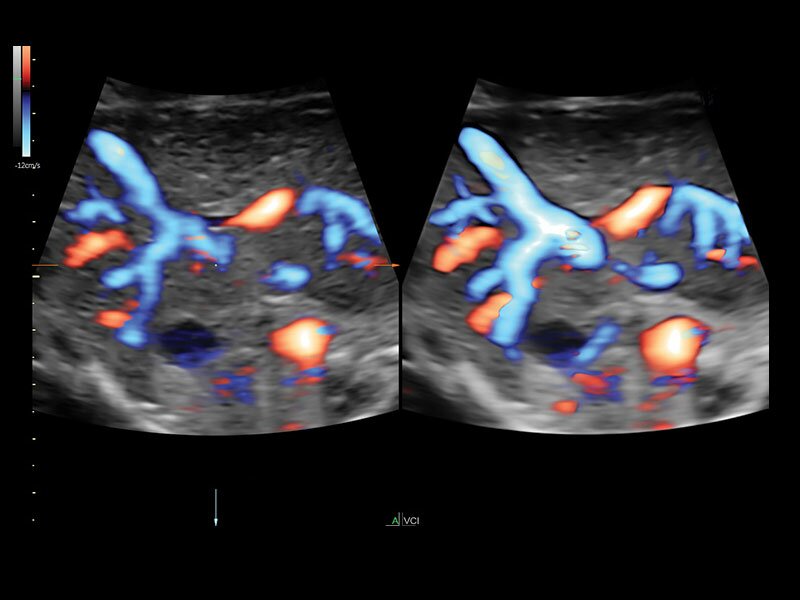

• Высокочувствительный допплер (HD-Flow)

• Реалистичный объёмный кровоток в режиме ЦДК (Radiantflow)

• HDlive Flow - перемещаемый источник света, совместимый с визуализацией кровотока в 3D

• HDlive Flow Silhouette - режим "Силуэт" с выделением границ полостей сердца и сосудов, совместимый с визуализацией кровотока

• Технология HDlive Flow — повышает реалистичность визуализации сосудистых структур, улучшая восприятие глубины (по сравнению с традиционным цветовым допплером и функцией HD-Flow).